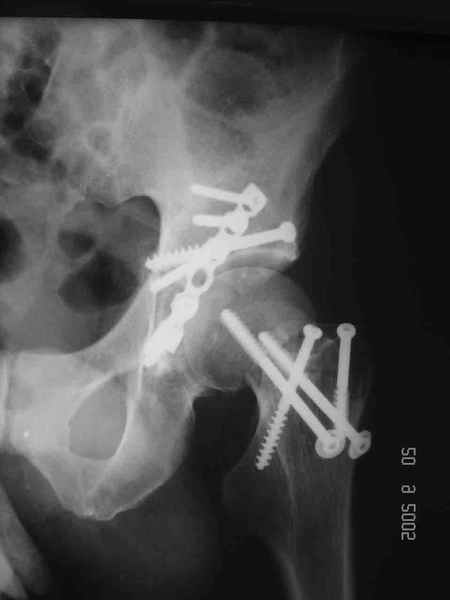

Уважаемые коллеги. Больной был оперирован в одну сессию 25 августа. Сначала на голень наложен спице-стержнвой аппарат. Затем выполнен остеосинтез вертлужной впадины Y-образным доступом. Пришлось дополнительно отсекать вертел. Шейка синтезирована спонгиозными винтами и спицами, вертел - спицами и стягивающей петлей. После операции находился на вытяжении 3 нед. Раны зажили первичным натяжением. Сейчас уже дома. Будет и дальше без нагрузки на левую ногу. Будем наблюдать в динамике. Ждем комментарии.

Перелом шейки был многооскольчатйй очень медиальный, по сути шейку и вертел расколотило об подвздошную кость с кучей мелких фрагментов, вертел был полностьб вовлечен в перелом, головка заподлицо скрывалась в расширенной вертлужной впадине. Качество кости приличное. Остатки дуги Адамса с предварительно проведенными винтами я вколотил в головку и компрессировал винтами - оказалось прочно, но образовался дефект верхнего отдела шейки, который был заплнен фрагментами фиксироваными трансфрактурными спицами - отсюда пучек.

Вертел во время доступа пришлось еще рубить, т.к.

переломы распространялись чересчур дистально.

Отсюда еще пучек спиц.